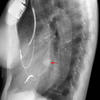

AzyEsop interf

Ex 1 arrows